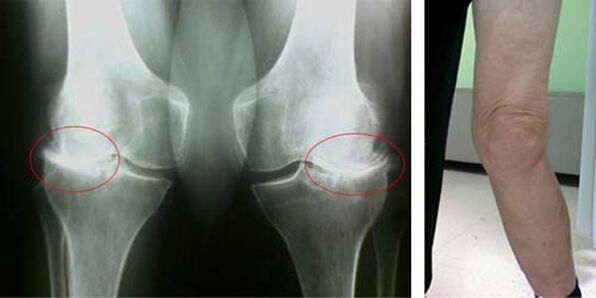

As fases iniciais da aparición dunha patoloxía como a artrose da articulación do xeonllo non se manifestan de xeito visual. Non obstante, despois dun período de tempo, o paciente comeza a notar sinais de deformidade do xeonllo, así como unha curvatura característica ao longo do eixe da perna inferior (dirixido cara a dentro). Tamén hai unha crise cando tes que dobrar a perna.

A presenza de dor e movemento limitado no xeonllo incita a unha persoa a ver un médico e someterse a un exame. Para iso, debe pasar probas e facer unha radiografía da articulación enferma. Se estas medidas non son suficientes para detectar a artrose da articulación do xeonllo, realízase unha resonancia magnética. En función dos datos recollidos, o médico selecciona os mellores métodos de tratamento.